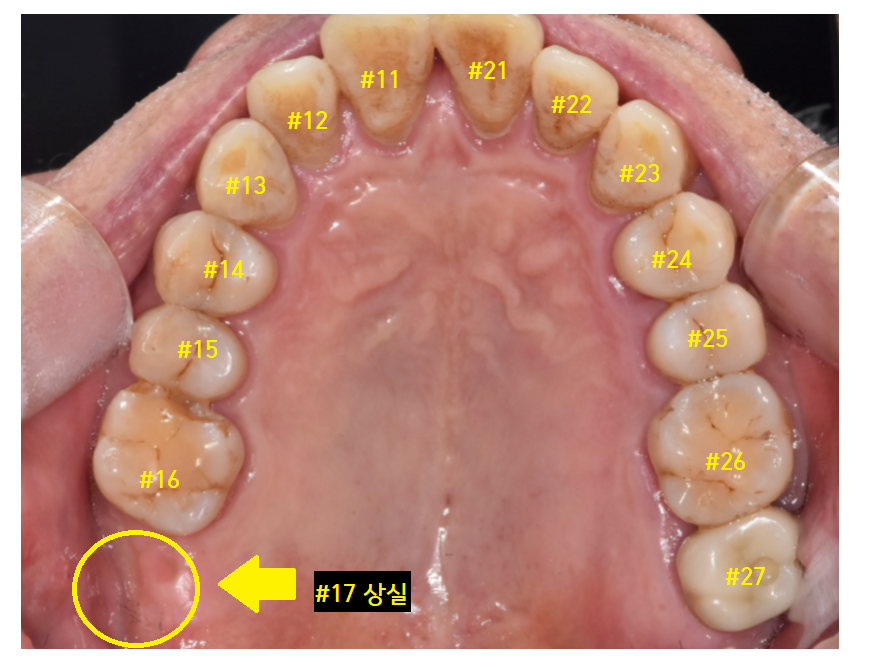

암사동 치과 환자분 사진을 함께 보실까요~?

- 윗니 맨 치아가 빠지고

아래 맨 끝 어금니가 물린다.

치아 개수가 하나가 비죠~?

오른쪽 맨 위 치아가 빠진 환자분입니다.

구강 내 사진을 보겠습니다.

#17 맨 끝 어금니가 한 개가 없네요.